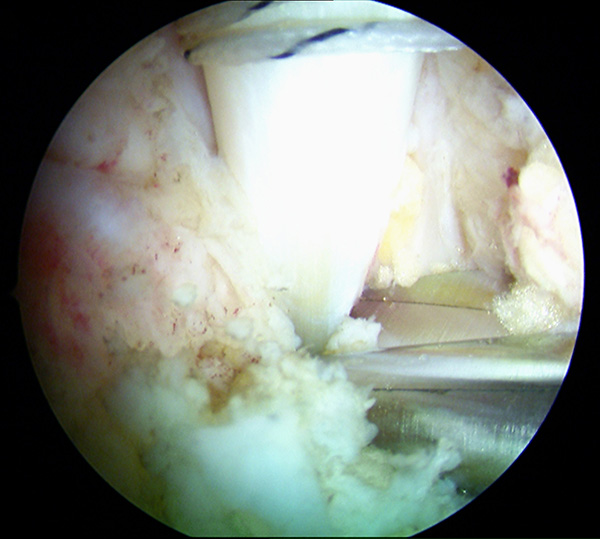

Abbildungen 5-8, Video 2

Anschließend wird die FHL-Sehne angeschlungen. Hierzu wird die Fadenschlaufe über das posteromediale Portal mit einer Fadenzange oder einem gebogenen Klemmchen um die FHL-Sehne geführt und anschließend wieder aus dem Portal herausgezogen. Nach Durchfädeln der freien Fadenenden durch die Schlaufe wird die Schlinge festangezogen. Die Technik wird in Video 2 demonstriert.

Zur Vollansicht bitte die Bilder anklicken. Fotos: M. Galla.